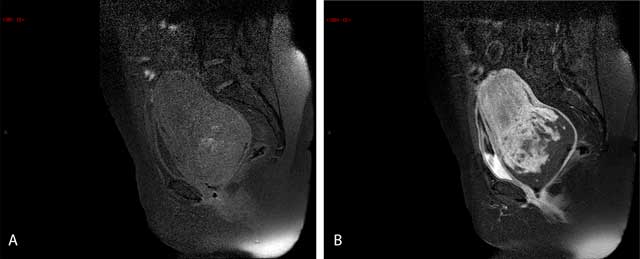

Figure 2

Sagittal T1-weighted (a, b) a. The bright spots of suppressed fat in the image denote hemorrhagic areas. b. After an injection of gadolinium, there is a heterogeneous enhancement of the mass.